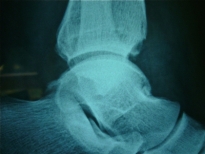

Exemple d'ostéochondromatose de la cheville gauche:

Dans ce cas, la limitation de la mobilité est due au volume des corps étrangers multiples.